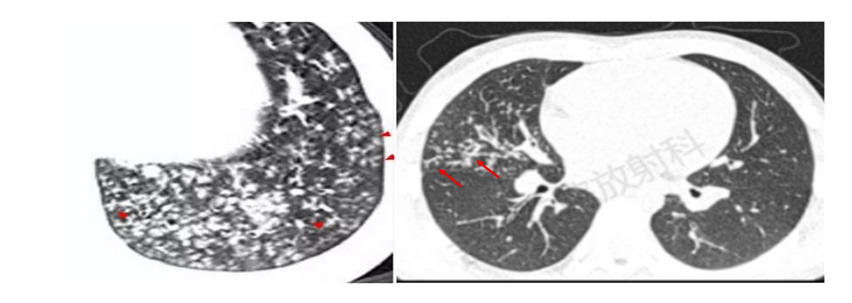

影像学检查尤其是CT是重要的检查手段,也是临床判断病情严重程度和评估预后的主要依据之一。支原体肺炎病理变化是首先侵犯气道粘膜上皮,引起支气管壁水肿增厚,接着向气道周围间质蔓延,引起肺间质充血、水肿及炎性细胞浸润,最后延伸至肺泡。在CT图像上主要有以下几种表现:

1.支气管壁增厚:支气管肺炎较可靠征象,支气管壁光滑、均匀增厚,可侵犯周围间质,周围边缘模糊,表现为支气管炎及周围炎,多由肺门向外周进展。

2.树芽征:细支气管或终末支气管内粘液阻塞,远端增粗,像树上发的新芽。

3.树雾征:支气管周围间质水肿,形成沿支气管蔓延的磨玻璃影,如同树周围的雾一样。

4.磨玻璃影:间质内水肿或部分肺泡内渗出,表现为磨玻璃样影。

5.大片实变:表现为中-高密度阴影,可有支气管气象,可伴有肺不张及胸腔积液,早期可表现为小叶中心结节影,随着病灶进展,进展为全小叶或更大范围。

随诊疾病的不同阶段,多种形态、大小不等和密度不均的病灶可混合出现,支气管壁增厚、树芽征、树雾征及实变影等征象可同时存在,结合咳嗽、发热等症状,可对支原体肺炎做出诊断。